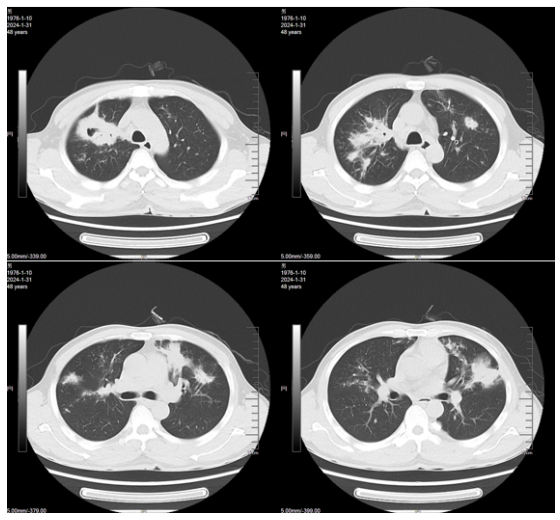

新冠病区诊治过程:鼻导管吸氧;阿兹夫定5 mg qd抗病毒、莫西沙星0.4 g qd抗感染,丙球10 g qd,地塞米松6 mg×2 d,之后予甲泼尼龙40 mg bid抗炎,低分子肝素钠5000单位ih q12h抗凝等治疗。2023年1月10日胸闷气急症状加重。血气分析(FiO2 41.0%):pH 7.39,PaO2 35.6 mmHg,PaCO2 34 mmHg,氧合指数87 mmHg。胸部CT(2023年1月10日,我院):双肺斑片影,符合病毒性肺炎,且较2023年1月6日明显加重(图1);双肾萎缩;双肾结石。

图片

图1  患者胸部CT

1月17日复查胸部CT:双肺磨玻璃影较前有所吸收(图2)

图2  复查胸部CT(2023-01-17)